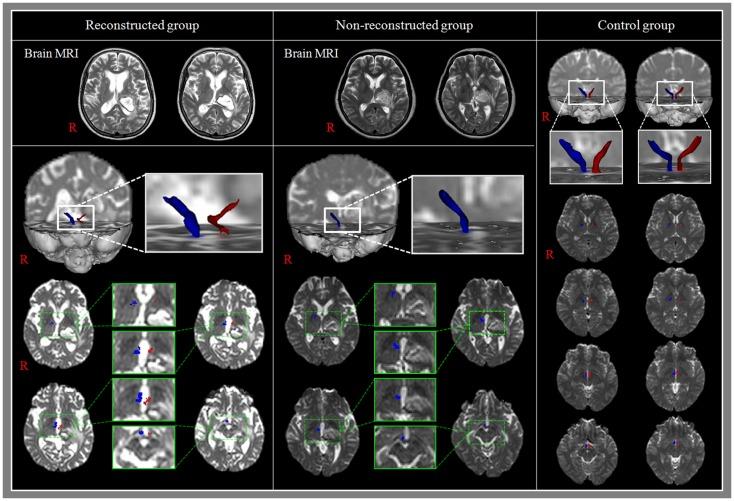

We recruited 22 patients with a thalamic hemorrhage and 20 control subjects. MTTs were reconstructed using the probabilistic tractography method. Patients were classified into two subgroups: reconstructed group, patients whose MTT was reconstructed in the affected hemisphere, and non-reconstructed group, patients whose MTT was not reconstructed.

Mammillothalamic tract was reconstructed in 5 (22.7%, reconstructed group) patients in the affected hemisphere and was not reconstructed in the remaining 17 patients (77.3%, non-reconstructed group). In addition, the MTT was not reconstructed even in the unaffected hemisphere in four patients (23.5%) in non-reconstructed group. Fractional anisotropy and mean diffusivity values of the affected hemisphere in reconstructed group also did not show significant differences from those in the unaffected hemisphere of reconstructed group and the control group (p > 0.05). However, the tract volume of the affected hemisphere in reconstructed group was significantly lower than that of the unaffected hemisphere in reconstructed group and the control group (p < 0.05).

A large portion of patients with thalamic hemorrhage appeared to suffer severe injury of the ipsilesional MTT (77.3%) and 18.2% of them appeared to suffer severe injury even in the contralesional MTT. In addition, the remaining 22.7% of patients who had preserved integrity of the ipsilesional MTT appeared to suffer partial injury of the ipsilesional MTT.